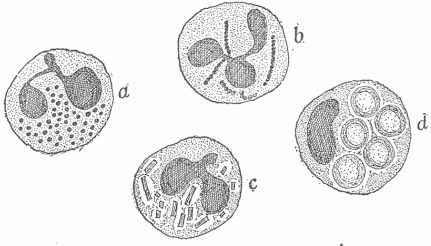

Fig. 12.—The Various Cells In The Blood. (a) The red blood cells, single and forming a roll by adhering to one another; (b) different forms of the white blood cells; those marked "1" are the most numerous and are phagocytic for bacteria.

The blood consists of a fluid, the blood plasma, in which numerous cells are contained. The most numerous of these are small cup-shaped cells which contain a substance called hæmoglobin, to which the red color of the blood is due. There are five million of these cells in a cubic millimeter (a millimeter is .03937 of an inch), giving a total number for the average adult of twenty-five trillion. The surface area of all these, each being one thirty-three hundredth of an inch in diameter, is about thirty-three hundred square yards. The hæmoglobin which they contain combines in the lungs with the oxygen in the inspired air, and they give up this indispensable substance to the cells everywhere in the body. There are also eight thousand leucocytes or colorless cells in a cubic millimeter of blood, this giving a total number of four billion in the average adult, and these vary in character and in relative numbers (Fig. 12). The most numerous of these are round and slightly larger than the red cells; they have a nucleus of peculiar shape and contain granules of a definite character. These cells serve an important part in infectious diseases in devouring and destroying parasites. They have power of active independent motion and somewhat resemble certain of the free living unicellular organisms. The blood plasma, when taken from the vessels, clots or passes from a fluid into a gelatinous or semi-solid condition, which is due to the formation within it of a network of fine threads termed fibrin. It is by means of the clotting of the blood that the escape of blood from ruptured vessels is arrested.